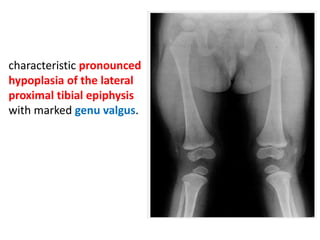

characteristic pronounced

hypoplasia of the lateral

proximal tibial epiphysis

with marked genu valgus.